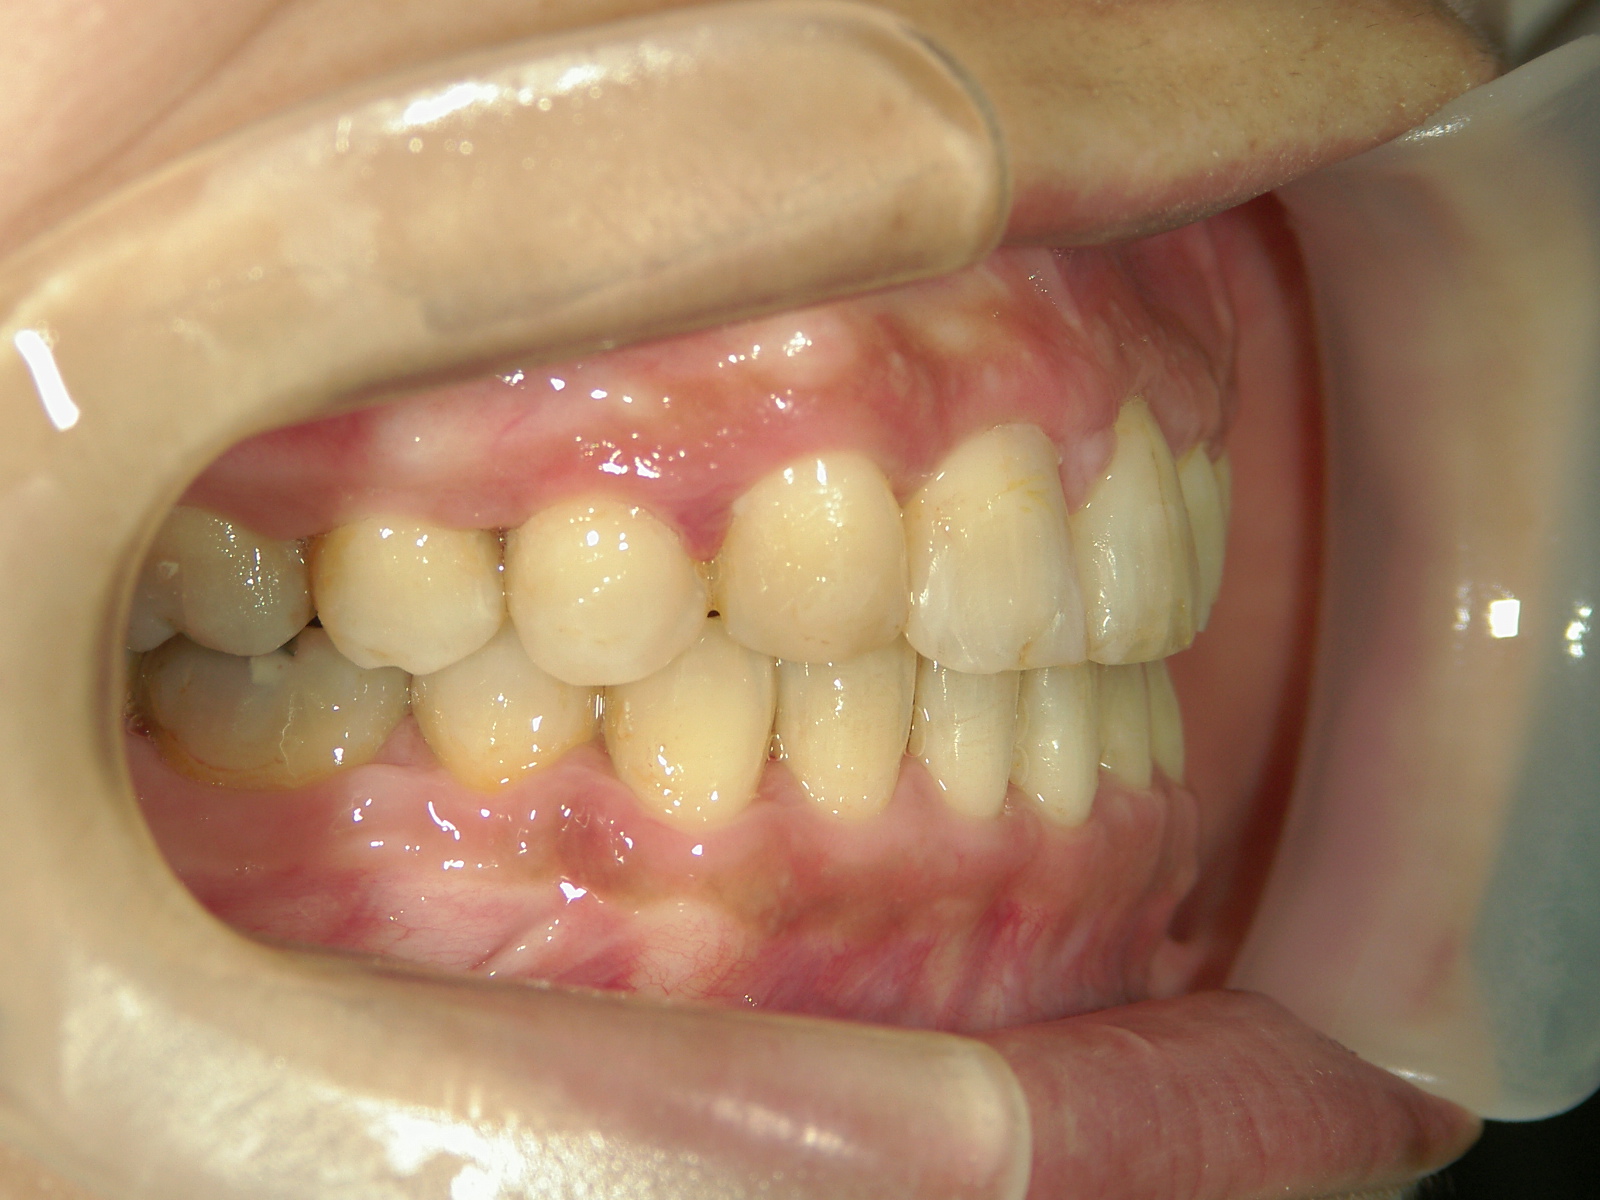

右上中切歯 抜歯後、空隙を閉鎖しました。

歯根の移動後、元々の中切歯の形に硬質レジンで歯冠を形態修正しました。

終了後に歯肉を形態修正しました。

・右上犬歯を移動して、開いたスペースへ移動。

・右上 第一小臼歯を移動して犬歯のスペースへ移動。